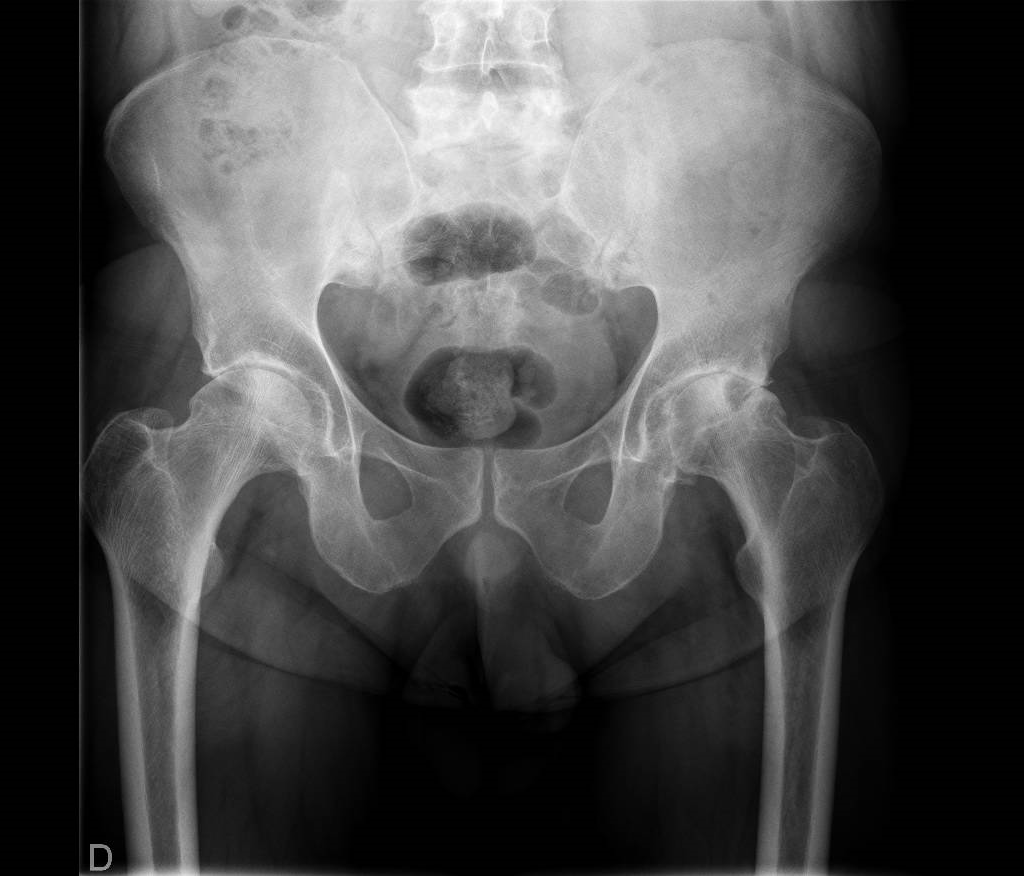

El diagnóstico se basa en la historia clínica, la exploración física y pruebas de imagen, como radiografías o resonancia magnética, para evaluar el grado de deterioro articular.